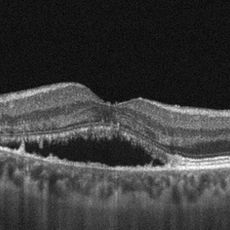

Una metodica recente è rappresentata dalla tomografia corneale con lampada rotante di Scheimpflug che consente un’analisi della cornea in tre dimensioni inclusa la superficie posteriore; questa metodica consente una diagnosi più precoce in caso di forme iniziali di cheratocono oltre che una pachimetria ottica in ogni singolo punto.

Le cheratoplastiche posteriori sono indicate nei casi in cui la funzione di pompa dell’endotelio, che rimuove attivamente l’acqua dallo stroma corneale, venga meno portando a progressiva imbibizione corneale e perdita di trasparenza. Pertanto, le principali indicazioni alle cheratoplastiche posteriori sono le patologie che compromettono la funzionalità dell’endotelio come la distrofia endoteliale di Fuchs, la cheratopatia bollosa in pazienti pseudofachici, o ancora le distrofie endoteliali congenite (CHED e PPD). Le due forme di cheratoplastica posteriore sono la DSAEK (Descemet Stripping Automated Endothelial Keratoplasty) e la DMEK (Descemet Membrane Endothelial Keratoplasty), che si distinguono tra loro per lo spessore della lamella trapiantata che nel caso della DSAEK comprende oltre al complesso Descemet-Endotelio anche un sottile strato di stroma profondo.

La DSAEK (Descemet Stripping Automated Endothelial Keratoplasty) è la tecnica di scelta nel trattamento dello scompenso corneale ed ha come finalità la sostituzione dell’endotelio corneale. La procedura consiste nel riempire la camera anteriore con aria e procedere alla rimozione con un uncino smusso del complesso endotelio-Descemet del ricevente in un singolo foglietto (stripping) lungo un’area circolare di circa 8 mm. La lamella corneale donatrice viene preparata rimuovendo lo stroma anteriore mediante microcheratomo con testina da 300-400 µm. La lamella posteriore così ottenuta viene poi punzonata per ottenere lo stesso diametro dell’area di endotelio rimosso dal ricevente ed inserita mediante apposito glide attraverso un tunnel nasale clear-cornea. Sotto il flusso continuo dell’irrigazione, la lamella donatrice si apre spontaneamente. Sia il tunnel clear-cornea che l’entrata laterale possono essere suturate con nylon 10-0 e la camera anteriore è totalmente riempita con aria.

La DMEK (Descemet Membrane Endothelial Keratoplasty) consiste nello stripping del solo complesso endotelio-Descemet del ricevente e la sostituzione dello stesso con il complesso endotelio-Descemet del donatore adeguatamente preparato. Essa condivide le indicazioni con la DSAEK, a differenza della quale, andando a rimpiazzare il solo endotelio con la rispettiva membrana di Descemet, dovrebbe avere un miglior risultato visivo in quanto si evita la creazione di interfacce stromali. I limiti della tecnica sono quelli di una più difficile curva di apprendimento e di una più difficile iniezione del lembo donatore, che essendo più sottile potrebbe non dispiegarsi correttamente o non aderire correttamente alla cornea ricevente (scompenso primario). La DMEK condivide con la DSAEK le complicanze post-operatorie quali il rigetto immunologico e lo scompenso tardivo del lembo.

LA DISTROFIA ENDOTELIALE DI FUCHS

È una patologia corneale caratterizzata da un progressivo e lento deterioramento dell’endotelio corneale; più comune nelle donne e generalmente esordisce a partire dalla mezza età. In questa patologia le cellule endoteliali, che normalmente hanno il compito di mantenere la cornea trasparente, vanno incontro a fenomeni di degenerazione che ne compromettono la sua funzione: la cornea si ispessisce e si riempie di acqua (edema), perde la sua trasparenza comportando una marcata e progressiva riduzione della vista; spesso può insorgere dolore acuto a causa della rottura delle bolle epiteliali. L’acuità visiva rimane normale durante le fasi iniziali della patologia; I pazienti affetti riferiscono inizialmente un appannamento della vista peggiore al mattino (con lieve miglioramento nel corso della giornata) poiché la cornea è più spessa al risveglio a causa della mancata evaporazione notturna; negli stadi avanzati la cornea resta opaca tutto il giorno senza miglioramenti.

Nella distrofia di Fuchs si possono distinguere tre fasi in base alla comparsa dei segni patognomonici della patologia corneale:

-

Graduale aumento della “cornea guttata centrale”, che conferisce all’endotelio un aspetto a “metallo battuto”;

-

Scompenso endoteliale con annebbiamento visivo che si riduce durante la giornata;

-

Edema stromale ed epiteliale persistente con formazione di bolle, “cheratopatia bollosa”, con dolore e fastidio se si verifica una rottura delle stesse; può sopraggiungere fibrosi stromale.

La terapia risolutiva è rappresentata dal trapianto di cornea, che attualmente è di tipo lamellare posteriore (DSAEK, UT-DSAEK o DMEK), con la sostituzione del solo strato endoteliale; tale procedura assicura un recupero funzionale molto più rapido rispetto ad una cheratoplastica perforante convenzionale e rischi intraoperatori decisamente ridotti.

MICROSCOPIA ENDOTELIALE

Consiste nella valutazione dello strato corneale più importante e profondo, l’endotelio, che con la sua costante attività mantiene trasparente la cornea.

Mediante apparecchiature dedicate, che richiedono, o meno, il contatto con l’occhio, si possono ottenere fotografie ad elevata risoluzione della superficie più interna della cornea; tali immagini sono successivamente elaborate da un sistema di analisi che ne definisce numerosi parametri, fra cui la densità cellulare, la regolarità di forma e la qualità del mosaico.

Questo esame è eseguito in tutte le patologie che interessano l’endotelio corneale (distrofie e degenerazioni endoteliali), ma soprattutto rientra negli esami preliminari da eseguire prima di chirurgia sul segmento anteriore (cataratta, glaucoma, trapianto di cornea) o in chirurgia refrattiva.